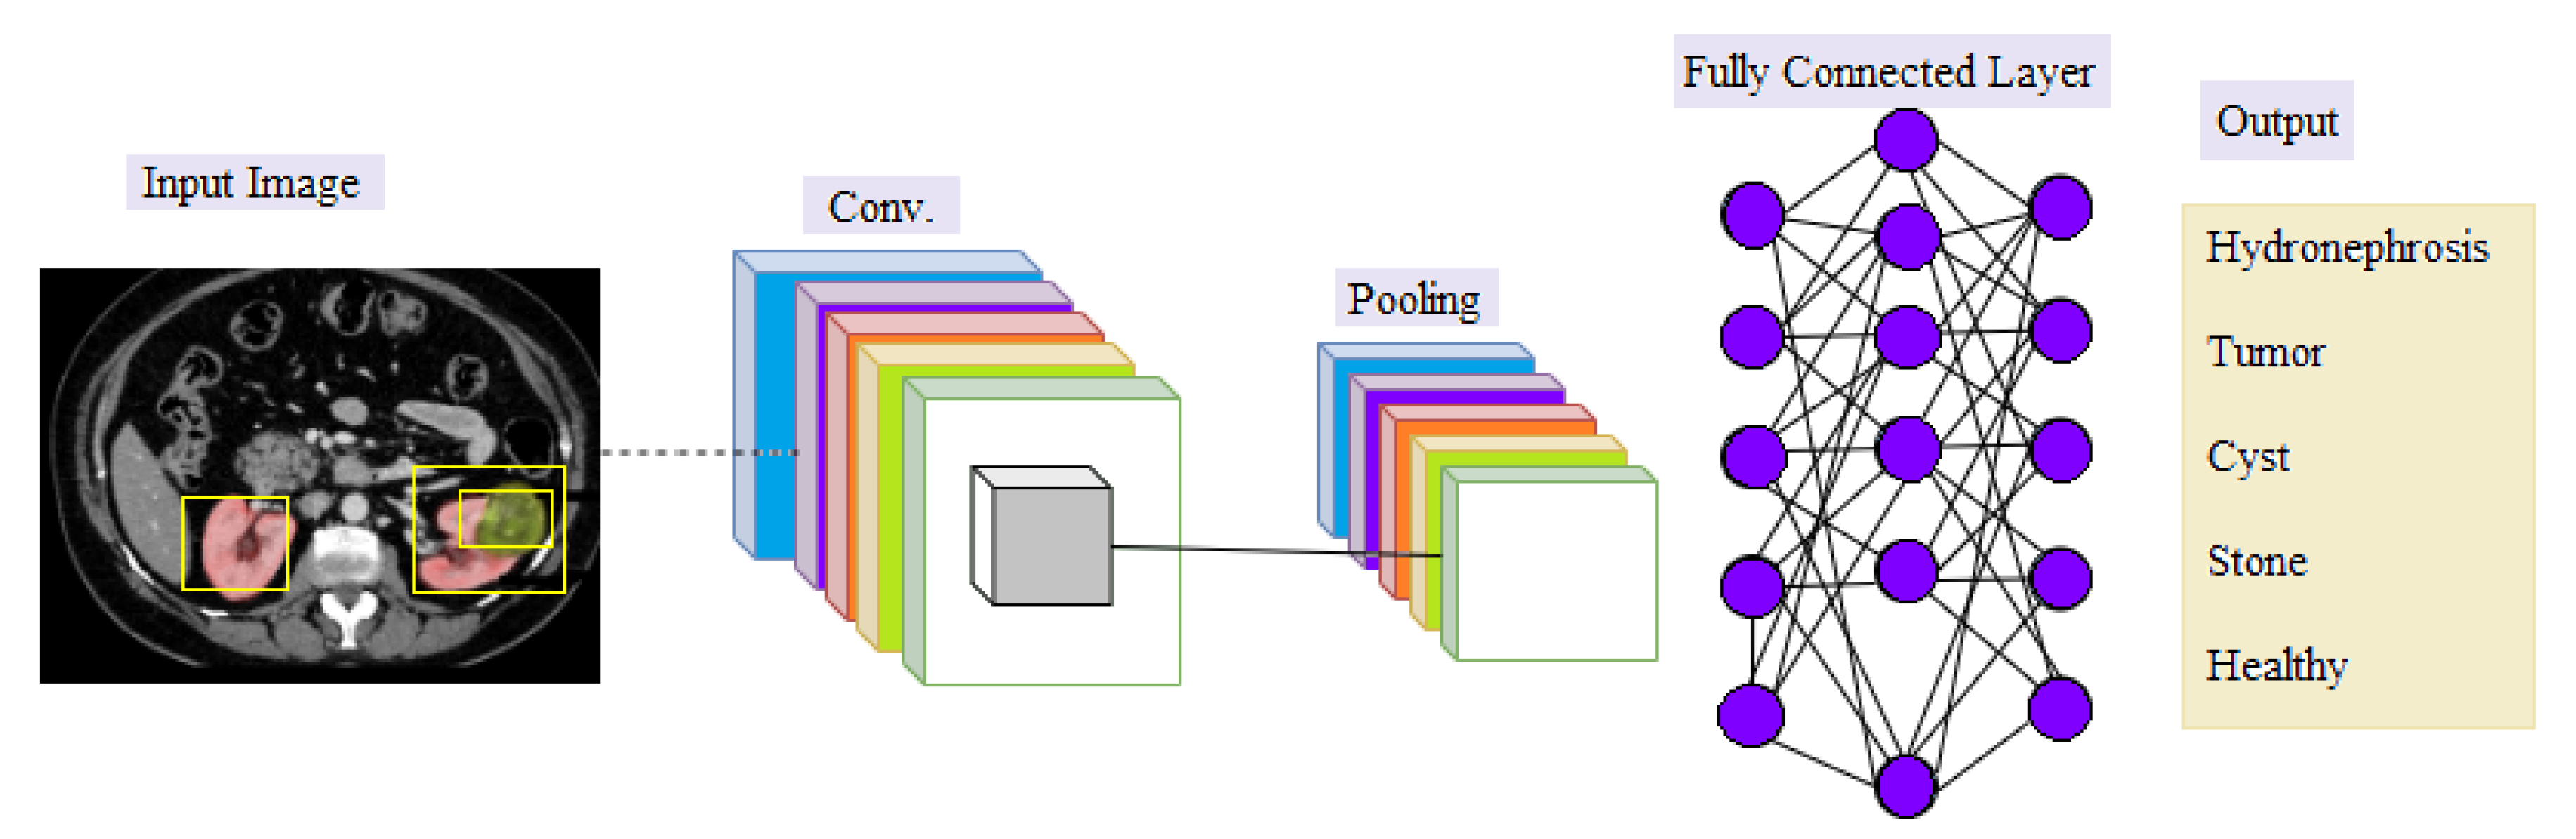

Convolutional Neural Network (CNN)

- Convolutional Layer: In the convolutional layer, a filter (known as a kernel) is used to determine the existence of patterns in the input images (original image), after which several filters can be employed to extract different features. The filter is a small size to have the ability to scan the whole image and apply the appropriate arithmetic between the filter and the pixels to extract the features. The filter settings are reset during the periodic training phase, and when the network has been trained for a sectionicular number of epochs (epochs imply all training samples have been entered simultaneously), these filters start looking for different characteristics in the image. Simple and evident features, such as edges in various directions, are extracted using the first hidden layers. The complexity of the attributes which must be recognized and extracted rises as we go deeper into the network’s hidden levels [42,43].

- Pooling Layer: The purpose of the pooling is to reduce the size of the activation maps. This is not necessary but prevents you from falling into an overfitting situation. The idea behind clustering is simple, as large arrays are scaled down [42].

- Fully-connected Layer: This layer is the last, where neurons are fully connected to all nodes of the previous layer. The final classification process takes place in it [44].